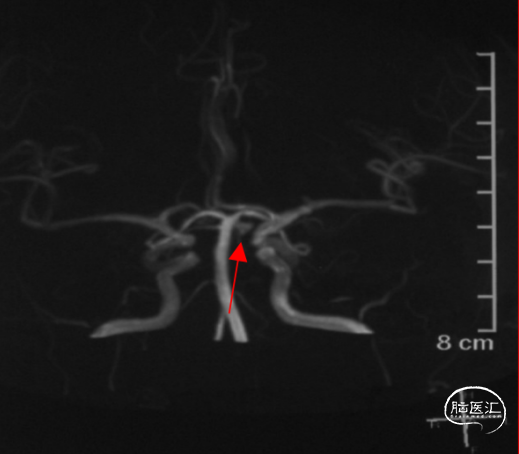

术前影像

术前影像

术前影像